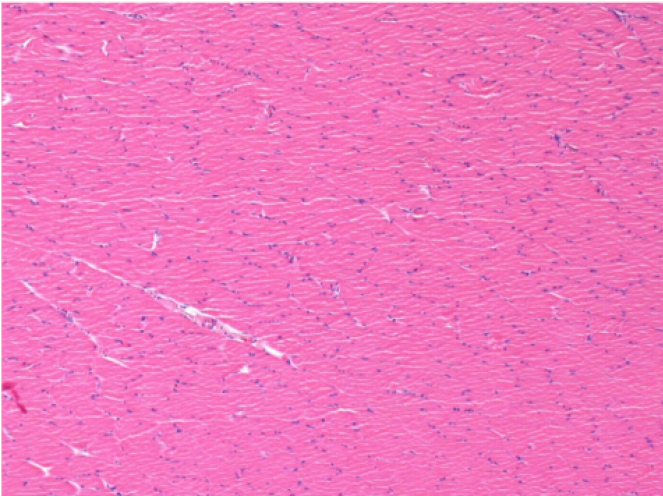

7 months (D210)after Endopeel IM Injection 0.1ml in the right pretibial muscle.

Complete Restitutio ad integrum after 7 months

L :Control 50xD210